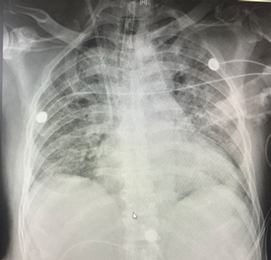

图5 患者8月5日胸部X线片

该患者本质上是由感染导致的血管炎,除了多脏器受损外,肺内应该还有出血。该患者的胸部CT比较有特点,呈向心性分布,这种情况除了考虑肺水肿、PCP、PAP外,也要考虑ANCA相关性血管炎和药物性肺损伤。该患者合并严重休克,所以还应考虑感染性疾病。二代测序结果结合临床还是有意义的,偶发分枝杆菌可以忽略,主要考虑钩端螺旋体病引起的感染。